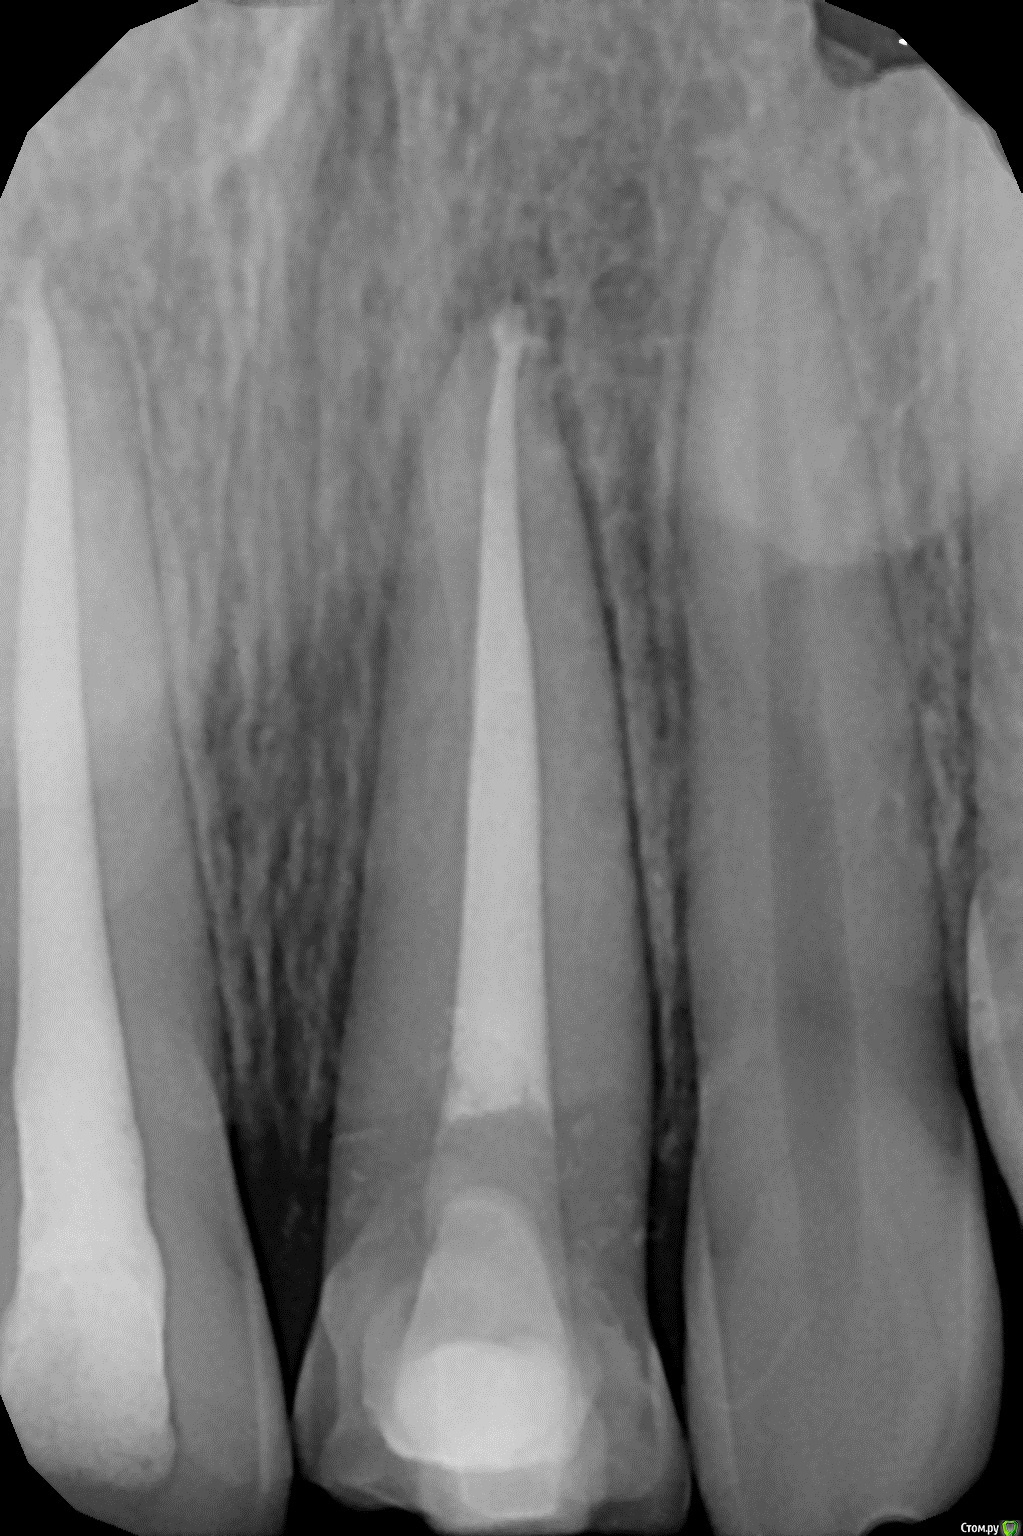

1586Doc Опубликовано 11 августа, 2017 Поделиться Опубликовано 11 августа, 2017 (изменено) Это обычная силиконовая каппа ?вытягиваем, потом стабилизация ? Как на долго? Изменено 11 августа, 2017 пользователем 1586Doc Ссылка на комментарий

kamranchick Опубликовано 11 августа, 2017 Автор Поделиться Опубликовано 11 августа, 2017 Это обычная силиконовая каппа ?вытягиваем, потом стабилизация ? Как на долго?капу сделали вакуум формером, помоему она пластмассовая вроде. стабилизация 2-3 месяца... Ссылка на комментарий